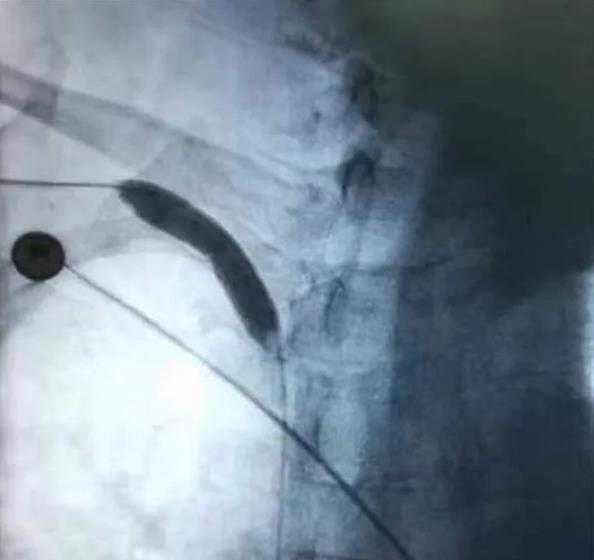

红河州第三人民医院肾内科主任周鹏宇,主任医师赵艳梅,充分了解患者病情,予患者行右上肢血管CTV检查提示:右侧头臂静脉狭窄。经过完善的术前讨论、评估,制定了DSA下经皮穿刺中心静脉球囊扩张术,必要时支架置入的手术治疗方案。近日,在介入科杨圣伟主任医师的协助下,成功为患者实施了右侧头臂静脉狭窄段球囊扩张术,术后造影,狭窄段回缩不明显,未予以置入支架。次日患者右上肢肿胀情况改善,看到这些惊喜的转变,患者及家属对手术的治疗效果十分满意。